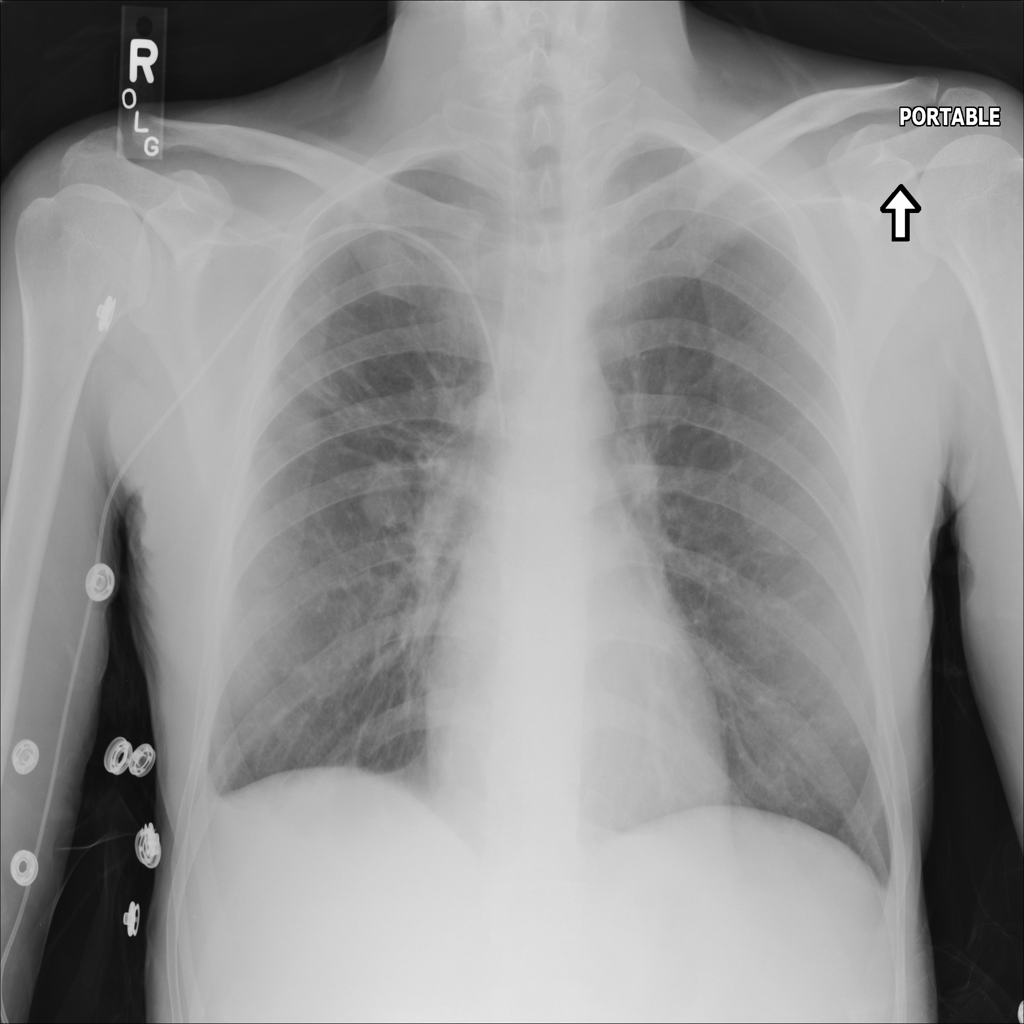

Mass

A mass is a larger focal opacity or lesion seen on the image. It is a descriptive finding that can have several causes and usually needs more imaging or clinical context to characterize.

PAT-4639 · IMG-024Mass

PAT-4639 · IMG-024

AP